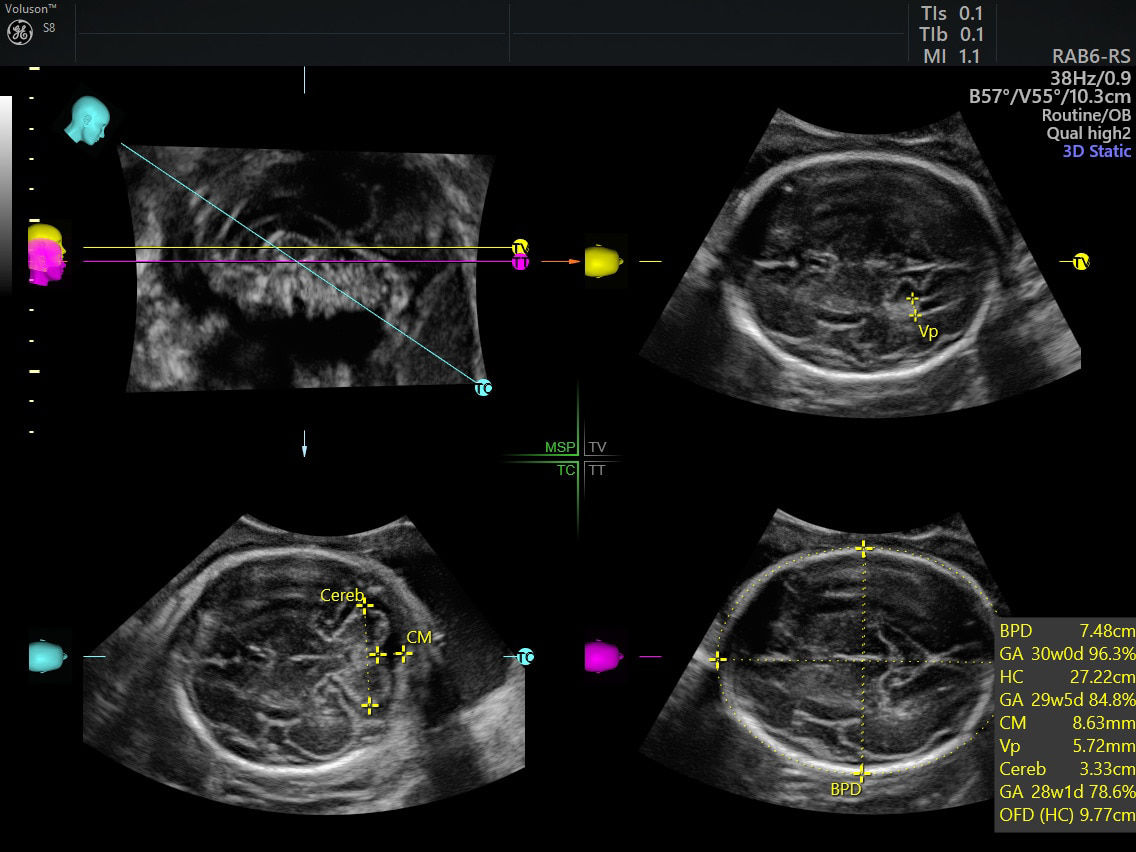

SonoCNS

Simplify assessment of the fetal brain with SonoCNS. This sophisticated, AI-powered, deep-learning technology helps properly align and display recommended views and measurements of the fetal brain.